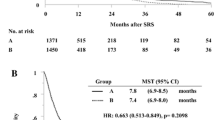

Demographic and clinical characteristics of the 49 patients in this study are presented in Table 1. The mean age of patients in the S + Cs-131 group was 65 years (range, 45–84 years) and in the S + SRS group it was 61 years (range, 32–84 years). The most common site of the metastatic tumors to the brain originated in the lungs, breast, and colon. All patients received surgery via a single craniotomy. The median radiation dose was 80 Gy for the S + Cs-131 group and 20 Gy for the S + SRS group. The median survival of S + Cs-131 and S + SRS were 15.5 and 11.3 months, and the 12 month survival rates were 61 and 49 %, respectively.

Additionally, evaluation of the cost-effectiveness using an ICER further shows the benefit of S + Cs-131. In the ICER analysis, summarized in Table 3, when compared to S + SRS, S + Cs-131, is viewed as being strongly dominant. A negative ICER value means that there is a less expensive and more effective treatment option, which in this case is S + Cs-131. Figure 1 compares the relative median survival times, 12 month survival rate, and hospital related costs between groups.